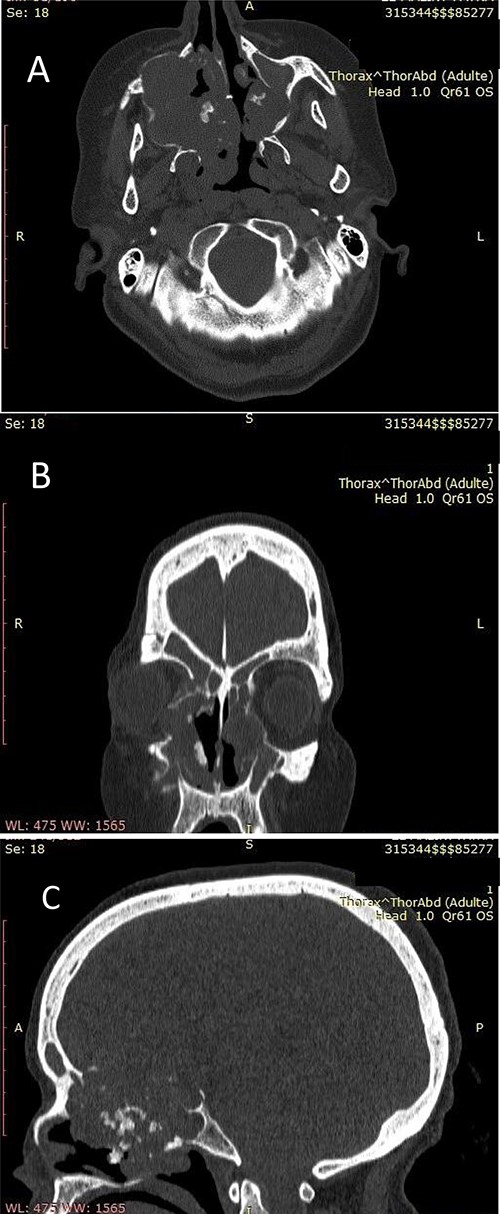

Our patient was a 55-year-old woman, without significant pathological history, presenting a right cheek swelling evolving over 1 year, with unilateral right nasal obstruction gradually becoming bilateral which was associated with a hyposmia, a bilateral exophthalmos, decrease bilateral deep visual acuity and intense permanent frontal headaches that were resistant to the usual analgesics. The clinical examination found a straight cheek and fixed painful mass of firm consistency, with irregular contours. The nasal flow was abolished on the right side and reduced on the left. Nasal endoscopy revealed a budding tumor process obstructing the two nasal cavities, without bleeding and it was masked by purulent secretions. Craniofacial computed tomography (CT) scan showed a large tumor process in the center of the nasosinusal region containing peripheral and central popcorn calcifications, with irregular contours, weakly enhancing after injection of contrast product and measuring ~65 × 62 mm (Fig. 1A–C; see Supplementary Material 1 for a detailed description). Magnetic resonance imaging (MRI) showed a lobulated, heterogeneous tissue process, hyperintense in T2, hypointense in T1. This tumor had a heterogeneous enhancement after injection of Gadolinium and measured 61 × 60 mm. It was also centering on the nasal cavities and on the ethmoid cells that caused lysis of the nasal turbinates and invaded the riddled blades of the ethmoid and with intra-orbital extension bilaterally (Fig. 2A–C; see Supplementary Material 1 for a detailed description). The histopathological analysis of the biopsy specimens found chondrosarcoma. An additional imaging based on thoraco-abdominal-pelvic CT scan did not show other locations. The patient underwent an endoscopic endonasal surgery that was incomplete due to the extension to the orbit and the brain (Fig. 3). The histopathologial analysis of the resected specimens confirmed the diagnosis of grade 2 chondrosarcoma (Fig. 4A and B). Our patient received adjuvant radiotherapy using a total dose of 50 Gy. After 6 months, post-therapeutic imaging based on CT and MRI showed a significant and clear decrease of the tumor volume with persistent residual tumor at the base of the skull given the incomplete excision. With a follow-up of 9 months, there was no recurrence.

(A) Nasosinusal CT in axial section showing an isodense tissue process, located in the right maxillary sinus and the ipsilateral nasal cavity, extended to the right anterolateral wall of the cavum and to the contralateral nasal cavity after lysis of the nasal septum, with calcifications. (B) Nasosinusal CT in coronal section showing the extension of the tumor process to ethmoidal cells and to the right orbit after lysis of the papery lamina. (C) Nasosinusal CT in sagittal section showing the extension of the tumor process to the ethmoid–sphenoid complex and to the frontal sinuses.